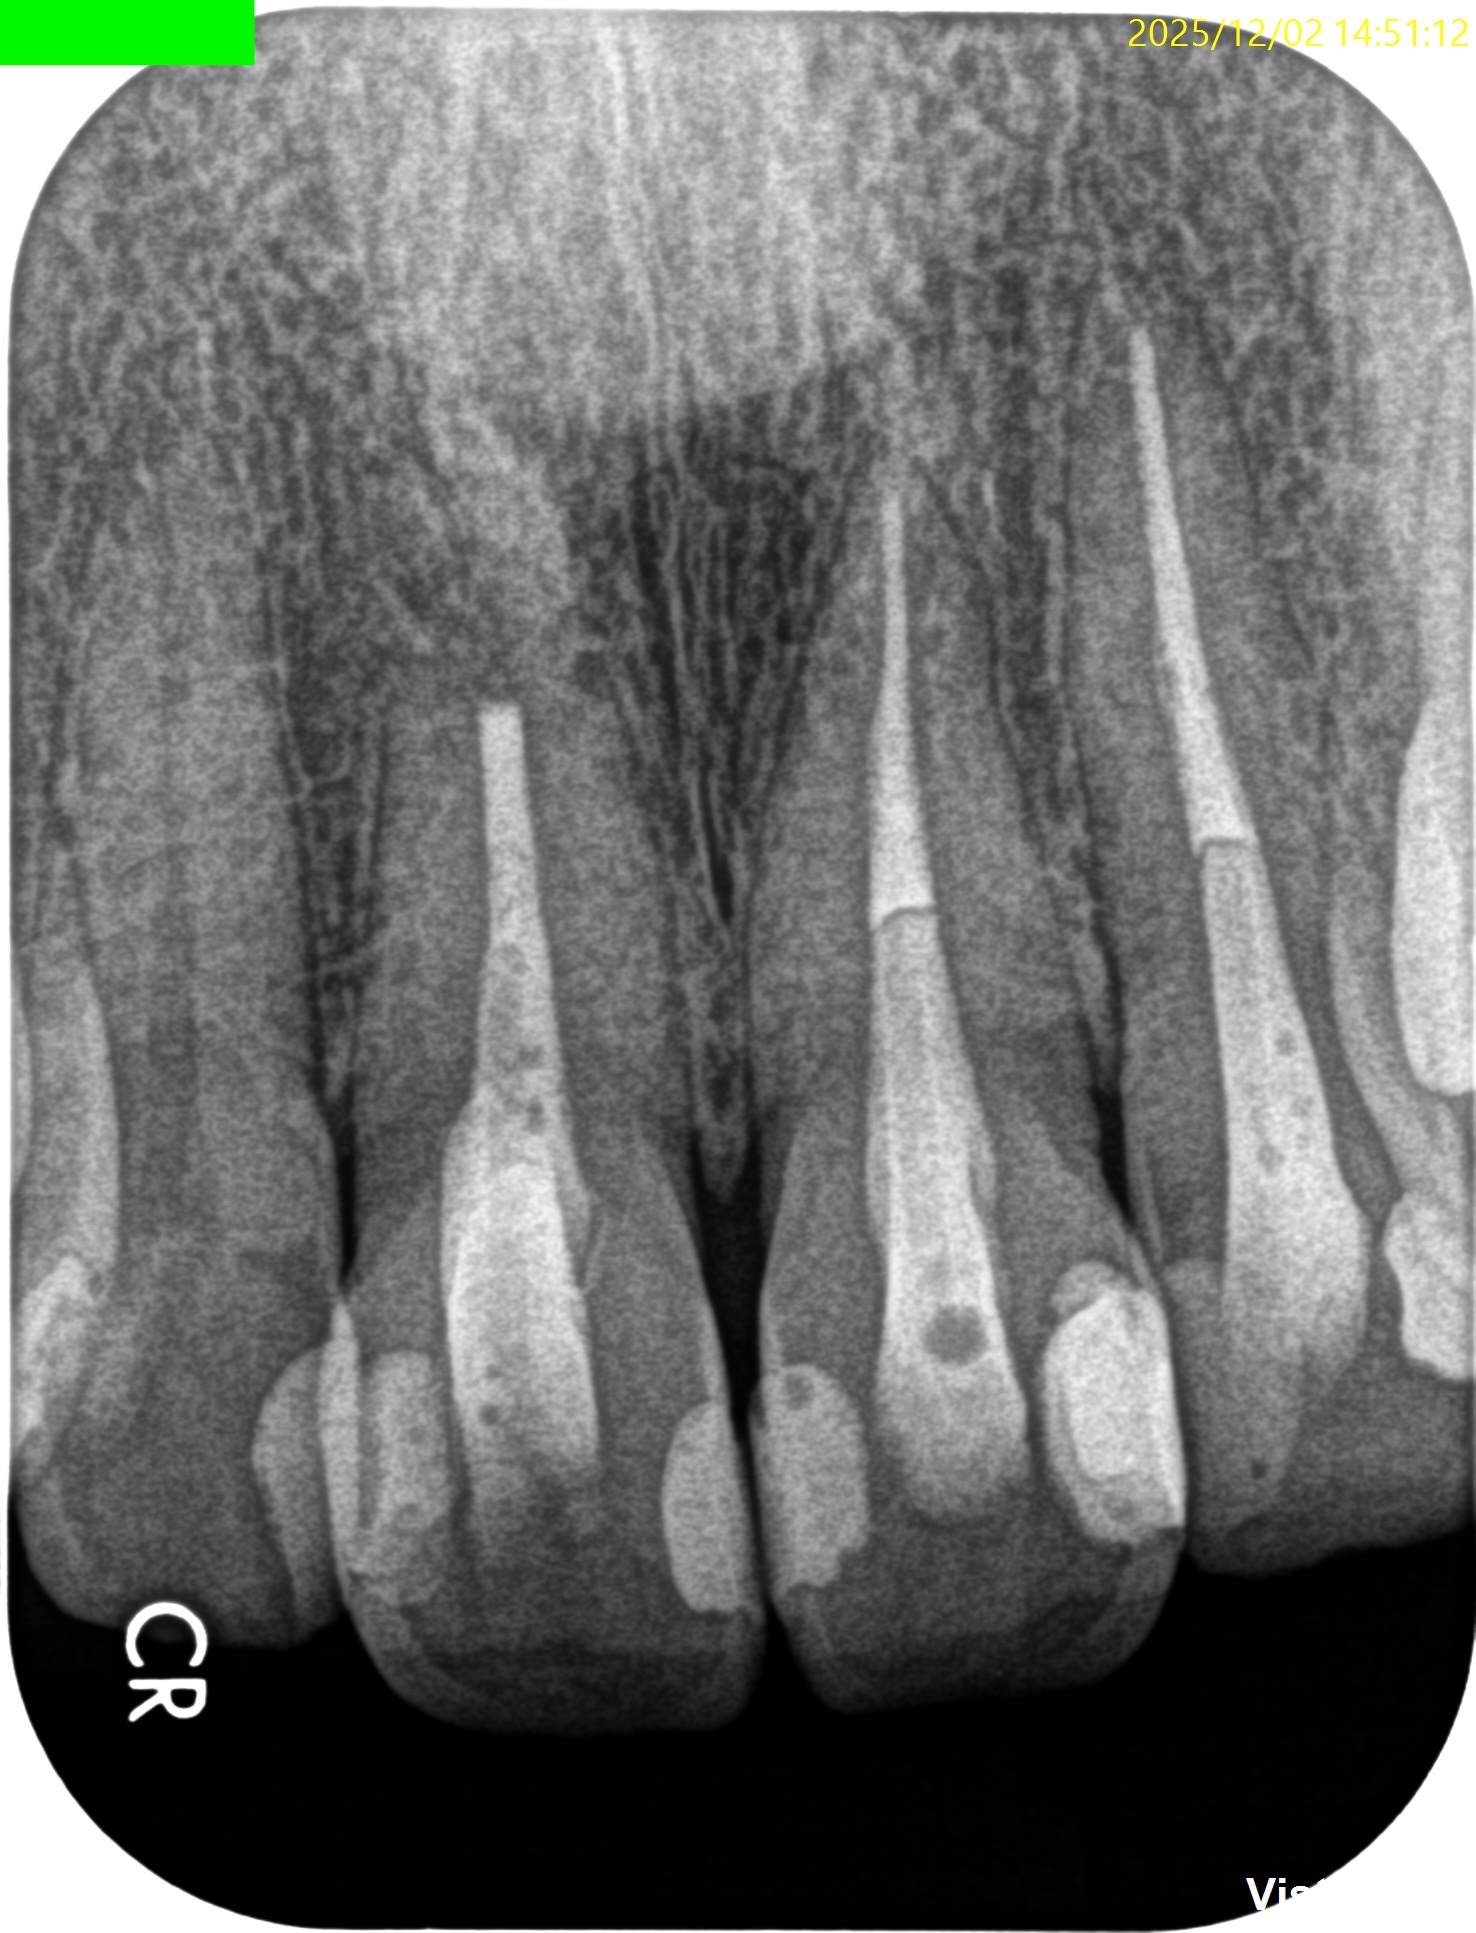

#8 Apicoectomy 6M recall(2025.12.2)

PA, CBCTを撮影した。

初診時と比較した。

劇的に状況は改善している。

#8,9,10に最終補綴もOKだろう。